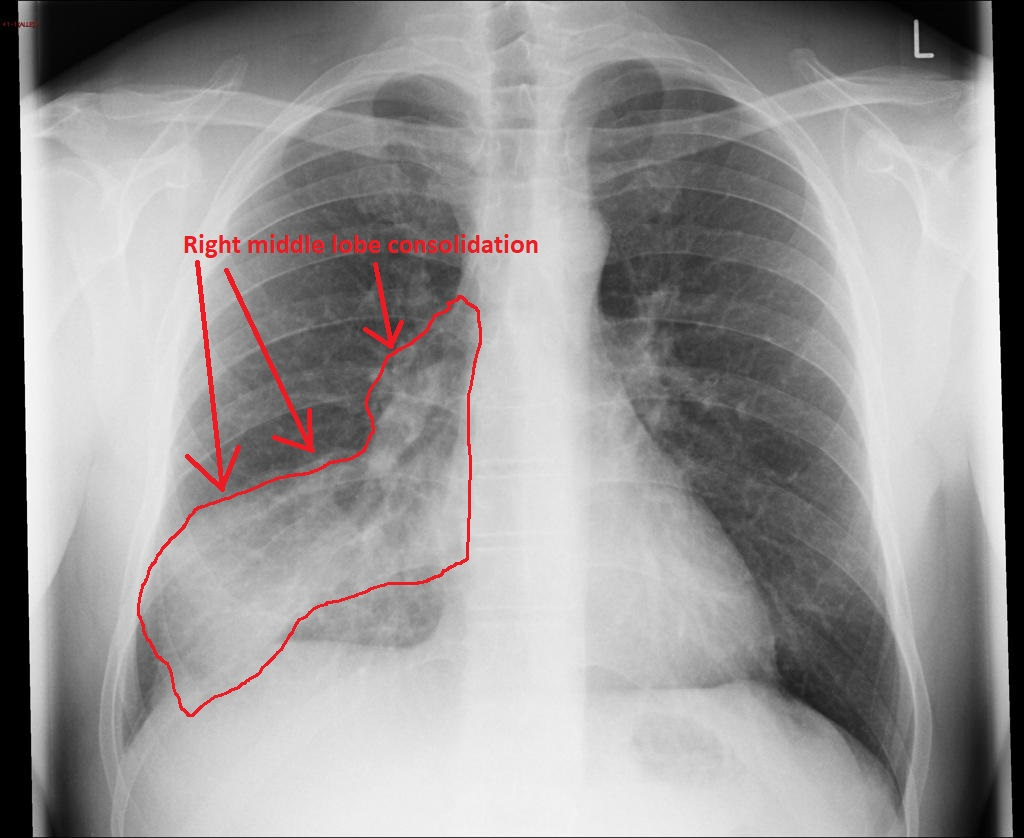

Вот так может выглядеть пневмония на рентгене

Рентген показал двухстороннюю пневмонию